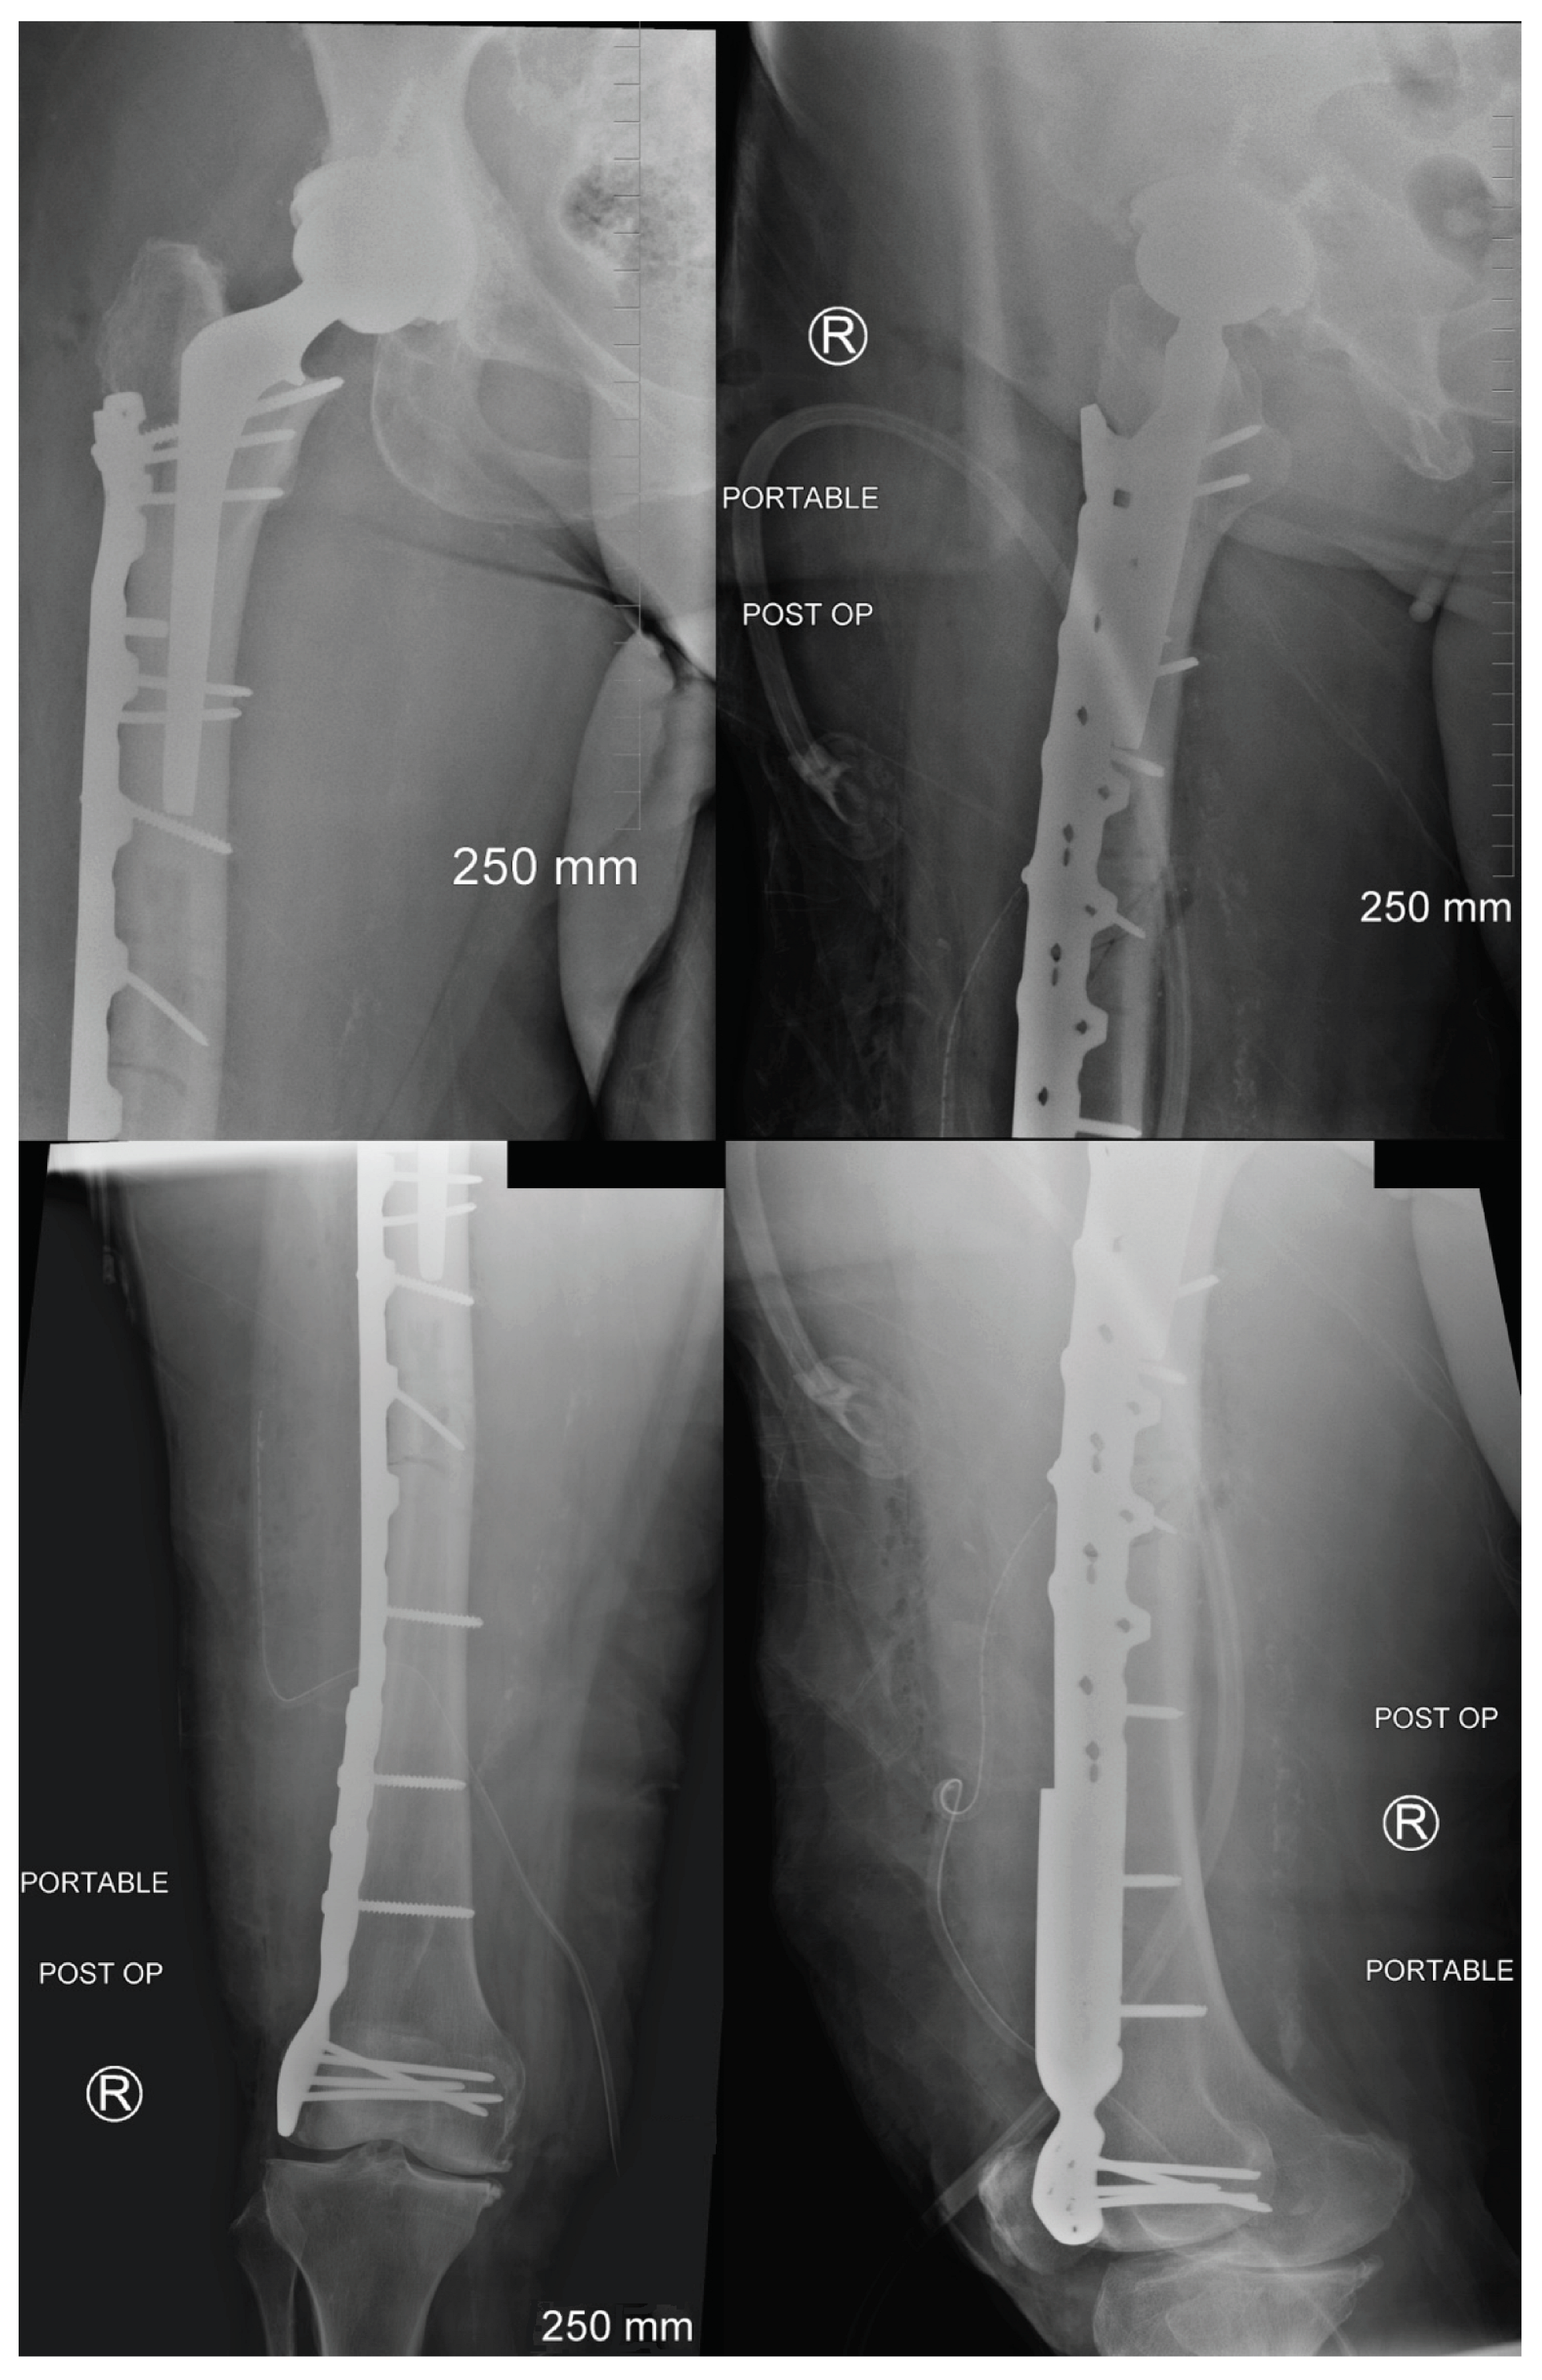

2. Case Description